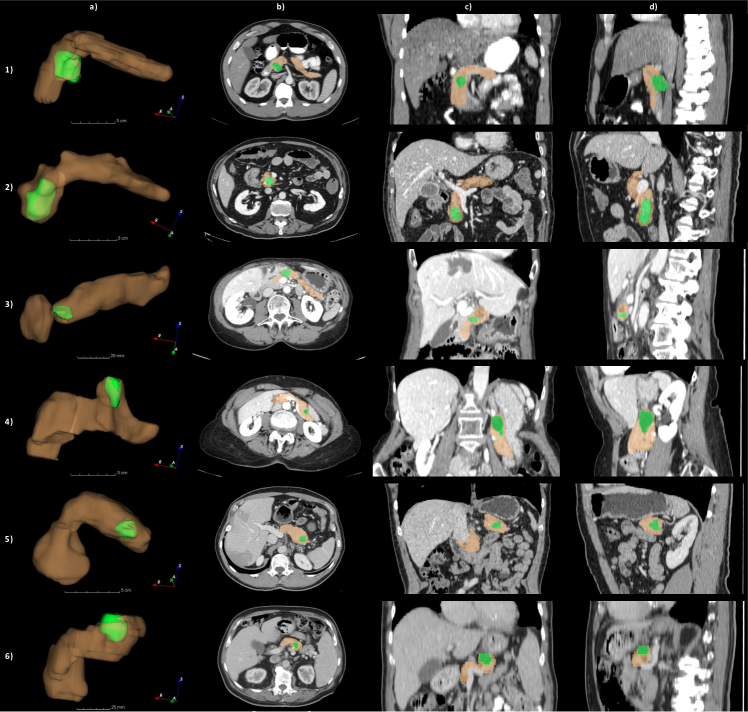

In order to provide an example of the variability of the pancreas parenchyma in terms of size and location, a registration was performed on 281 CTs of the MSD dataset using Elastix software (Klein et al., 2010), adapting inter-subject registration parameters from the study by Qiao et al. (2016) to the CT domain. Subject 29 of MSD was considered a reference image by virtue of its high-quality image and centrality within the range of variations observed in the dataset. A Hounsfield unit (HU) from 100 to 500 was used for all the images to improve the registration process, enhancing bones and brighter abdominal structures. The results are illustrated in Fig. 10. A histogram with the frequency distribution is shown in Fig. 11. It was created by measuring the volumetric distances from the centroid of the pancreas in subject 29 of MSD to the centroids of the pancreas from all other subjects after performing the registration.